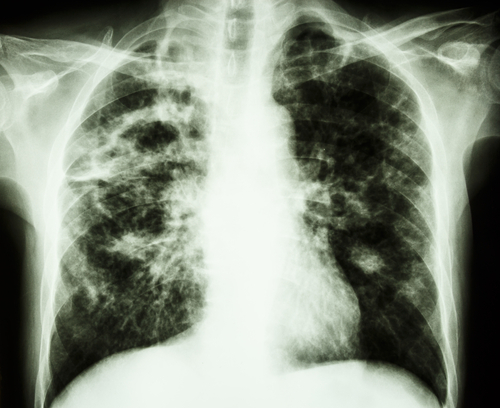

Pulmonary fibrosis, an ongoing process of scarring that leaves patients chronically short of breath, can progress in severity until the only course of treatment is the lung transplant. "This is the first paper to show that rather than being a 'second hit' to help initiate the disease, blocking lipid synthesis alone -- with no other insult to the lungs -- can instigate fibrotic scaring," said researcher Ross Summer.

But in earlier work, Drs. Summer and Romero have shown that when lung tissue is injured - by things like viral infection, particulate inhalation, or other insults - lung cells eventually stop producing lipids in order to conserve energy for other cellular repairs. In this study, the teams of Drs. Summer and Romero used a drug that inhibited lipid production in the lung and showed that this drug alone was capable of instigating lung fibrosis. In the converse experiment, the group showed that when increasing lipid production in lungs of animals already injured and developing pulmonary fibrosis, lung scarring could be reduced by 70-80 percent.